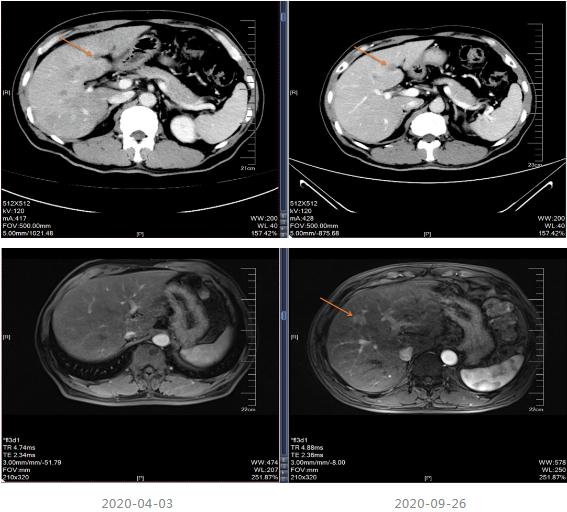

局部治疗:2020-09-26复查MRI提示部分病灶较前缩小,部分增大,于2020-10-22至武汉同济医院行“肝脏病灶微波消融术”,后继续口服卡培他滨至2021-5。

2021-06-08至2021-12-11采用“贝伐珠单抗+Cap”治疗8个周期。

2021-12-15影像学复查提示疾病进展。